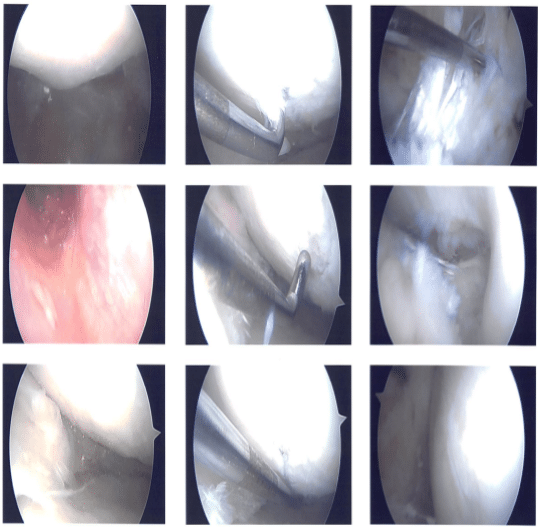

Lateral entry portal was used following an incision. Arthroscope was entered. Patellofemoral compartment and medial and lateral gutters showed normal anatomy. Pictures were taken.

Examination of the medial tibiofemoral compartment showed grade 3 to grade 4 osteochondral damage of the medial femoral condyle as well as degeneration of the medial meniscus and tearing.

There was grade 1 to grade 2 osteochondral damage of the medial tibial plateau also. There were no loose bodies out of the meniscus. Examination of the intercondylar notch showed degenerated and ruptured ACL.

Examination of the left tibiofemoral compartment showed lateral grade 3 to grade 4 osteochondral damage of the left femoral condyle and tear of the posterior horn of the lateral meniscus and undersurface of the meniscus.

Intraoperative images